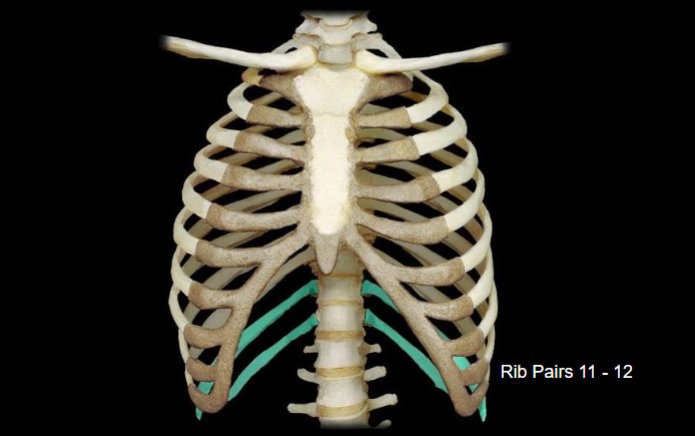

What bone is highlighted in this image?

What type of ribs are highlighted in this image?

vertebral (false, floating) ribs (the two bottom ribs in the back)